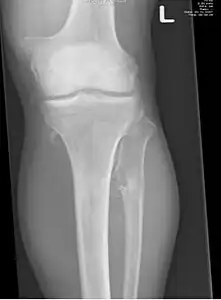

Multiple osteochondromas causing deformity of the forearm (shortening of the Radius with secondary bowing of the Ulna). -